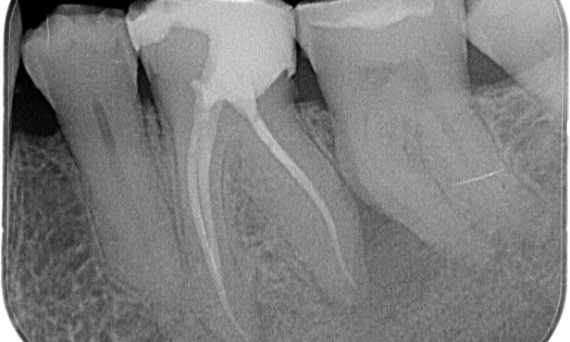

Vóór: Periapicale radiolucentie aan de distale wortel en verlies van lamina dura aan de mesiale wortel.

Na: TruNatomy werd voor deze casus gekozen om een cariësgerichte benadering en een focus op pericervicale dentineconservering mogelijk te maken, vooral op het mesiale aspect waar de tand een meer minimale restauratie had.